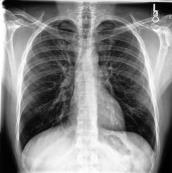

Large numbers of labeled medical images are essential for the accurate detection of anomalies, but manual annotation is labor-intensive and time-consuming. Self-supervised learning (SSL) is a training method to learn data-specific features without manual annotation. Several SSL-based models have been employed in medical image anomaly detection. These SSL methods effectively learn representations in several field-specific images, such as natural and industrial product images. However, owing to the requirement of medical expertise, typical SSL-based models are inefficient in medical image anomaly detection. We present an SSL-based model that enables anatomical structure-based unsupervised anomaly detection (UAD). The model employs the anatomy-aware pasting (AnatPaste) augmentation tool. AnatPaste employs a threshold-based lung segmentation pretext task to create anomalies in normal chest radiographs, which are used for model pretraining. These anomalies are similar to real anomalies and help the model recognize them. We evaluate our model on three opensource chest radiograph datasets. Our model exhibit area under curves (AUC) of 92.1%, 78.7%, and 81.9%, which are the highest among existing UAD models. This is the first SSL model to employ anatomical information as a pretext task. AnatPaste can be applied in various deep learning models and downstream tasks. It can be employed for other modalities by fixing appropriate segmentation. Our code is publicly available at: https://github.com/jun-sato/AnatPaste.